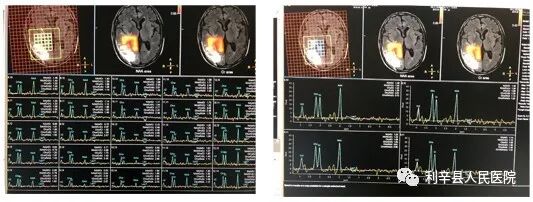

他与科室同事钻研开展各项磁共振新技术新业务,如头颅波谱、灌注、胎儿胎盘、乳腺、不需要造影剂肾动脉血管和下肢动脉血管业务,在周边市县级医院处于领先水平,得到三级医院专家认可。